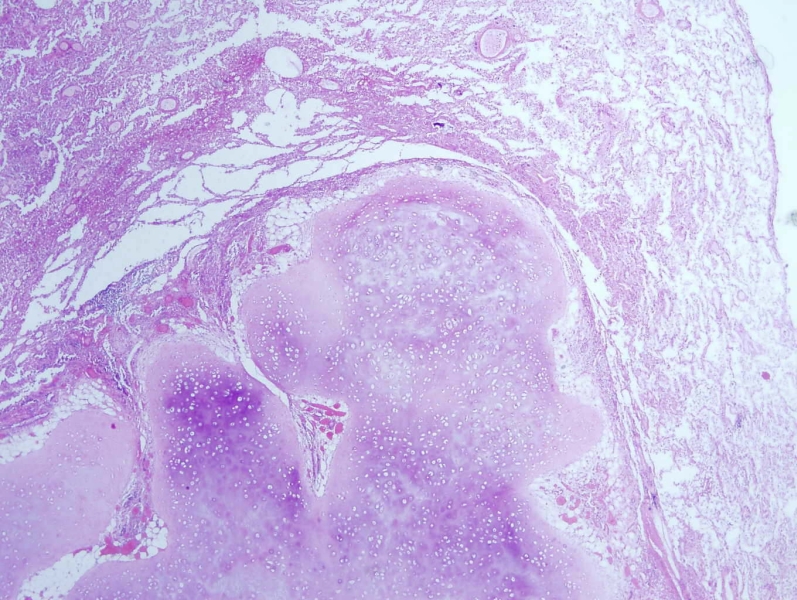

Карнификация Легкого: Микропрепараты и Диагностика

Раздел: Калейдоскоп образов